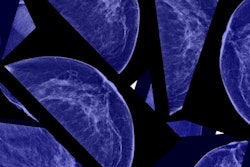

Breast screening should be offered to women starting at age 40, but screening should start only after a woman discusses the best age at which to begin with her physician, according to updated guidelines released June 22 by the American College of Obstetricians and Gynecologists (ACOG).

The updated guidelines represent a double-edged sword for mammography proponents. On the positive side, ACOG continues to support 40 as the age at which mammography should be considered, in line with imaging groups such as the American College of Radiology and the Society of Breast Imaging. On the negative side, ACOG no longer backs routine mammography starting at 40, instead recommending that a shared decision-making process begin at that time.

The updated guidelines begin by noting that research supports the idea that mammography screening starting at age 40 reduces breast cancer mortality in average-risk women. However, breast screening also involves potential harms, including anxiety, overdiagnosis, and false-positives, according to ACOG.